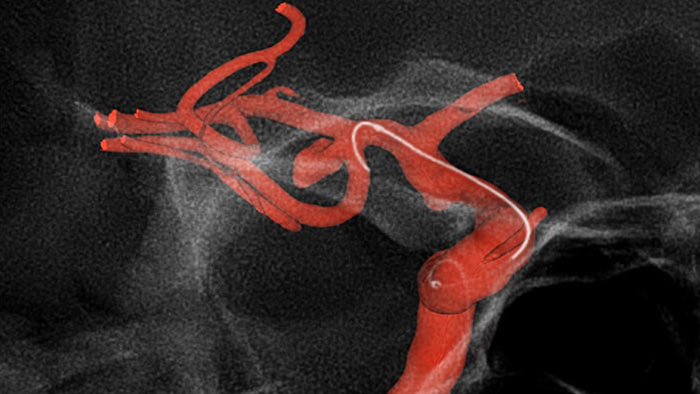

Navegue con precisión utilizando la guía de imágenes 3D dinámicas

Visualización mejorada de SmartCT Roadmap

SmartCT Roadmap mejora la visualización de vasos superpuestos para apoyar la navegación precisa de la aguja guía y el catéter a través de vasculatura compleja. Ofrece precisión de alto nivel con compensación en tiempo real para los movimientos del gantry, de la mesa y los pequeños movimientos del paciente.